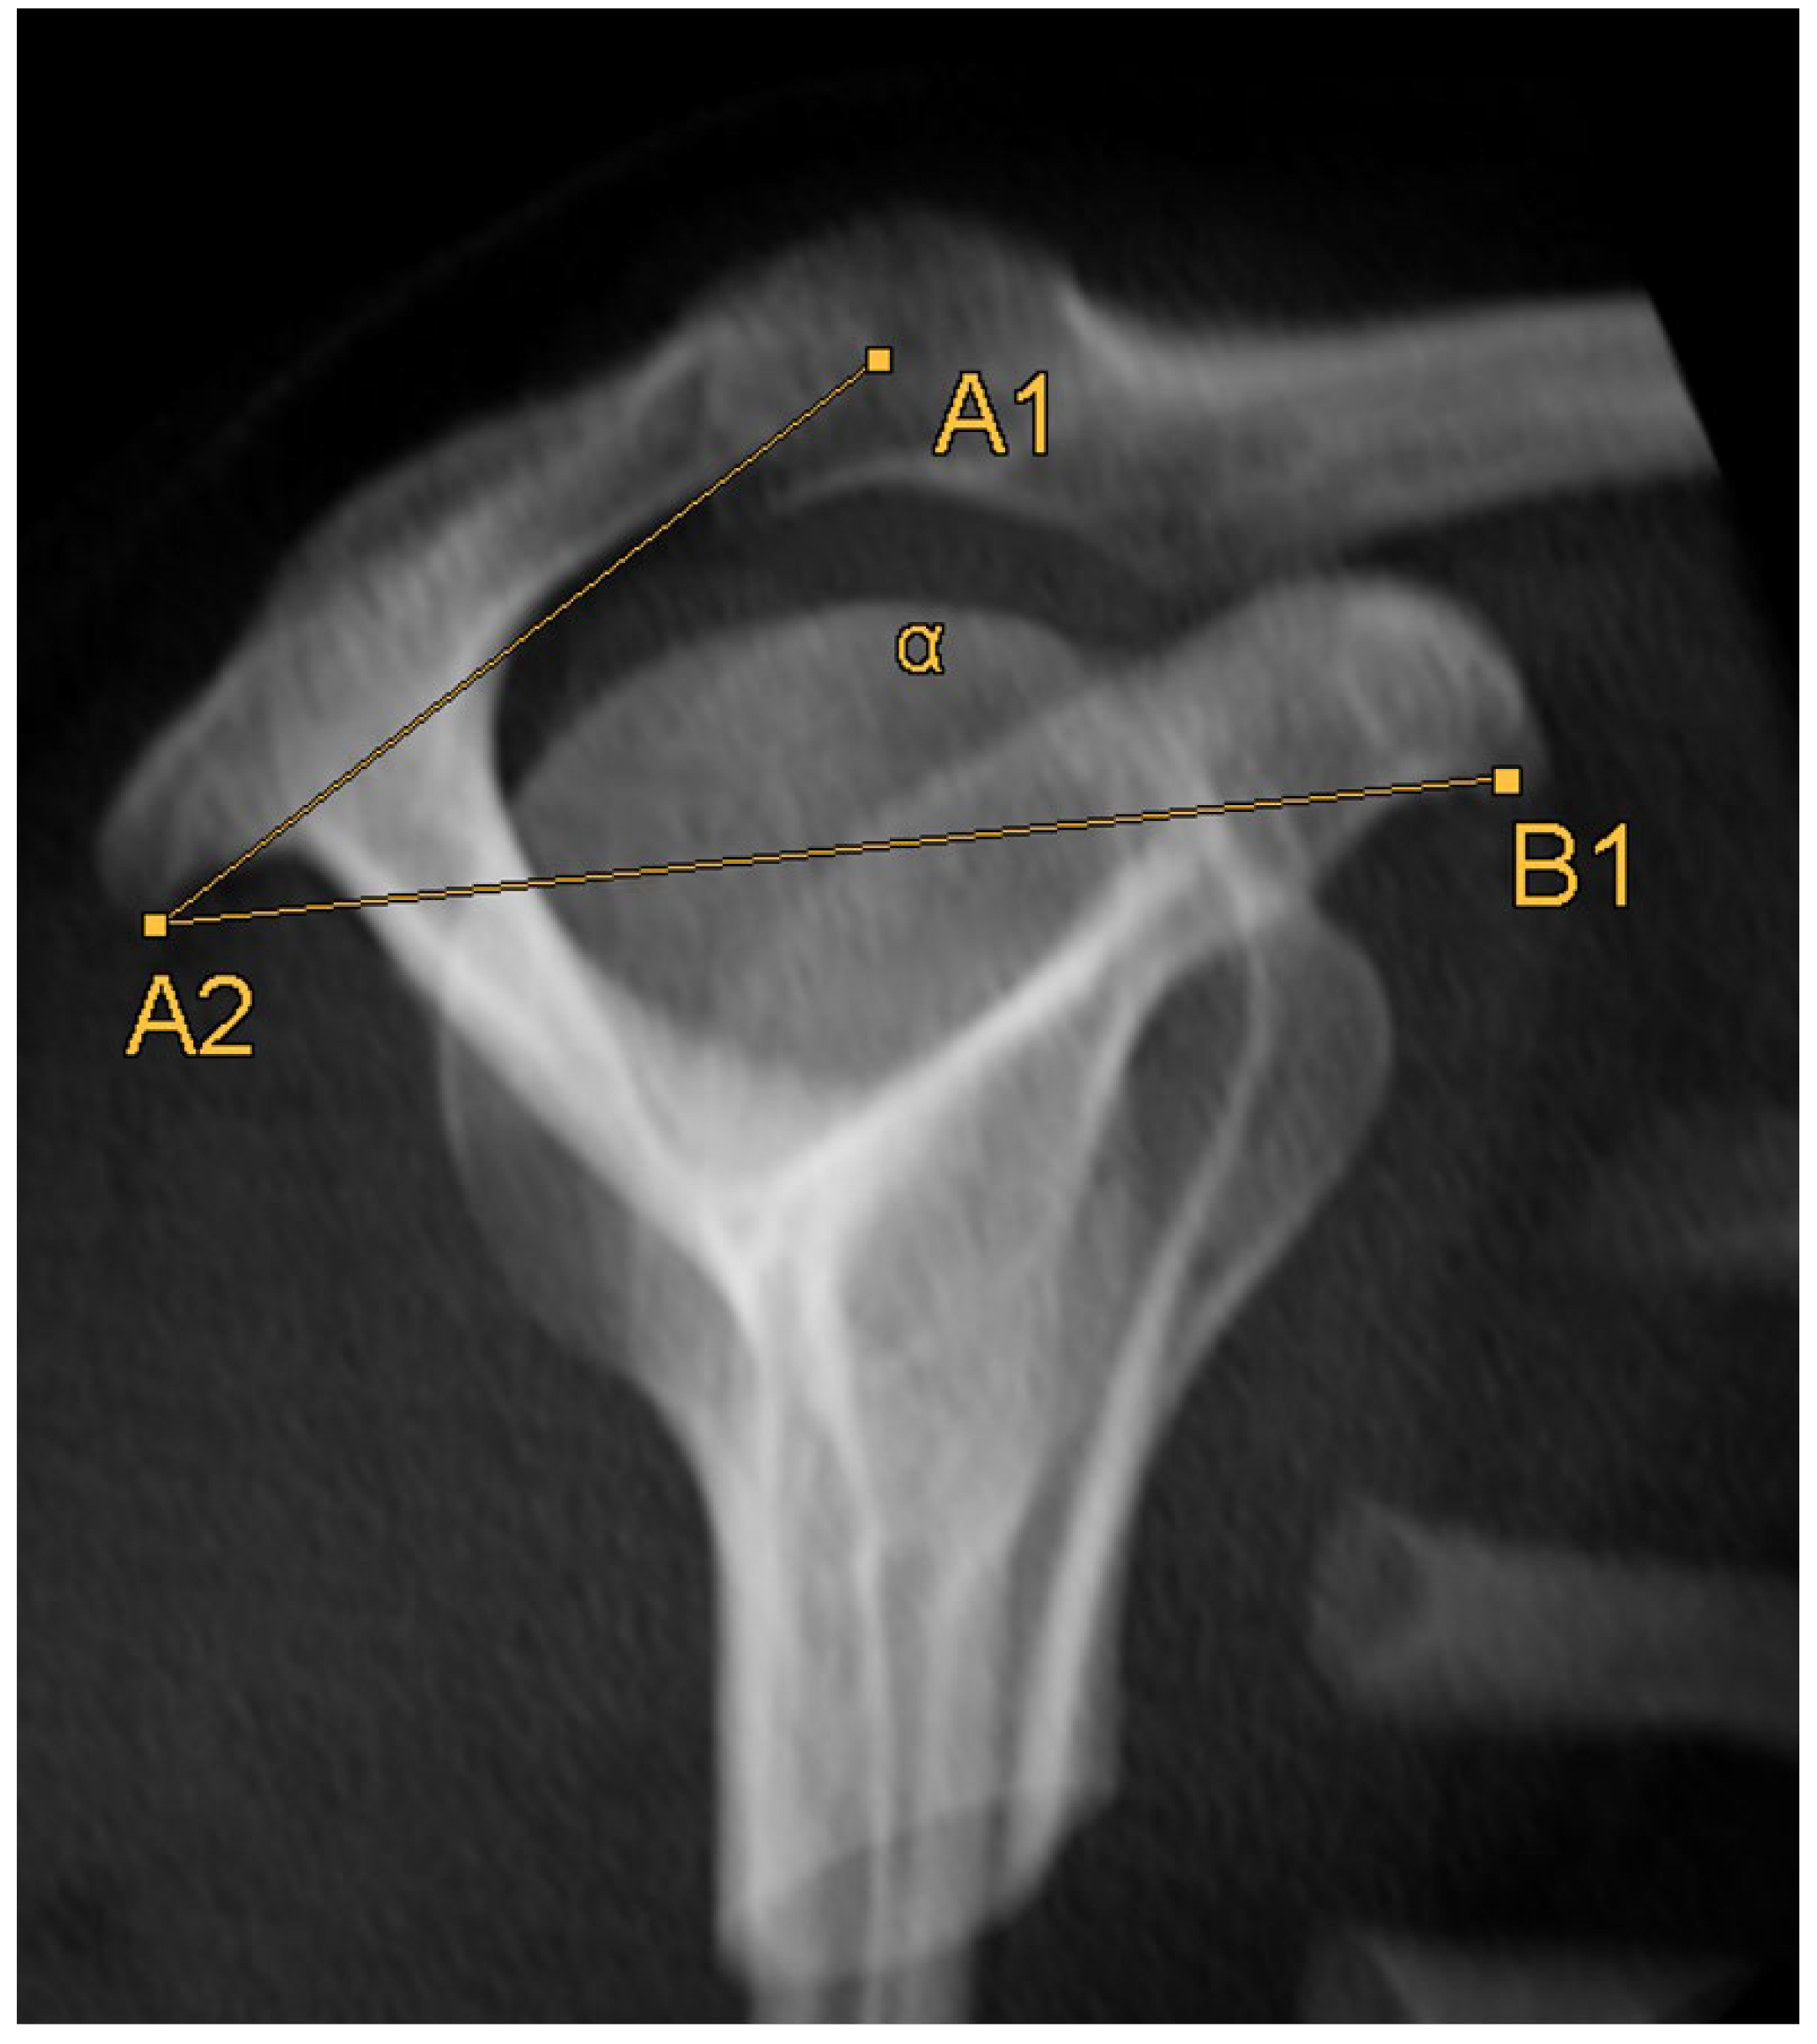

2.3. Acromion Index (Figure 1)